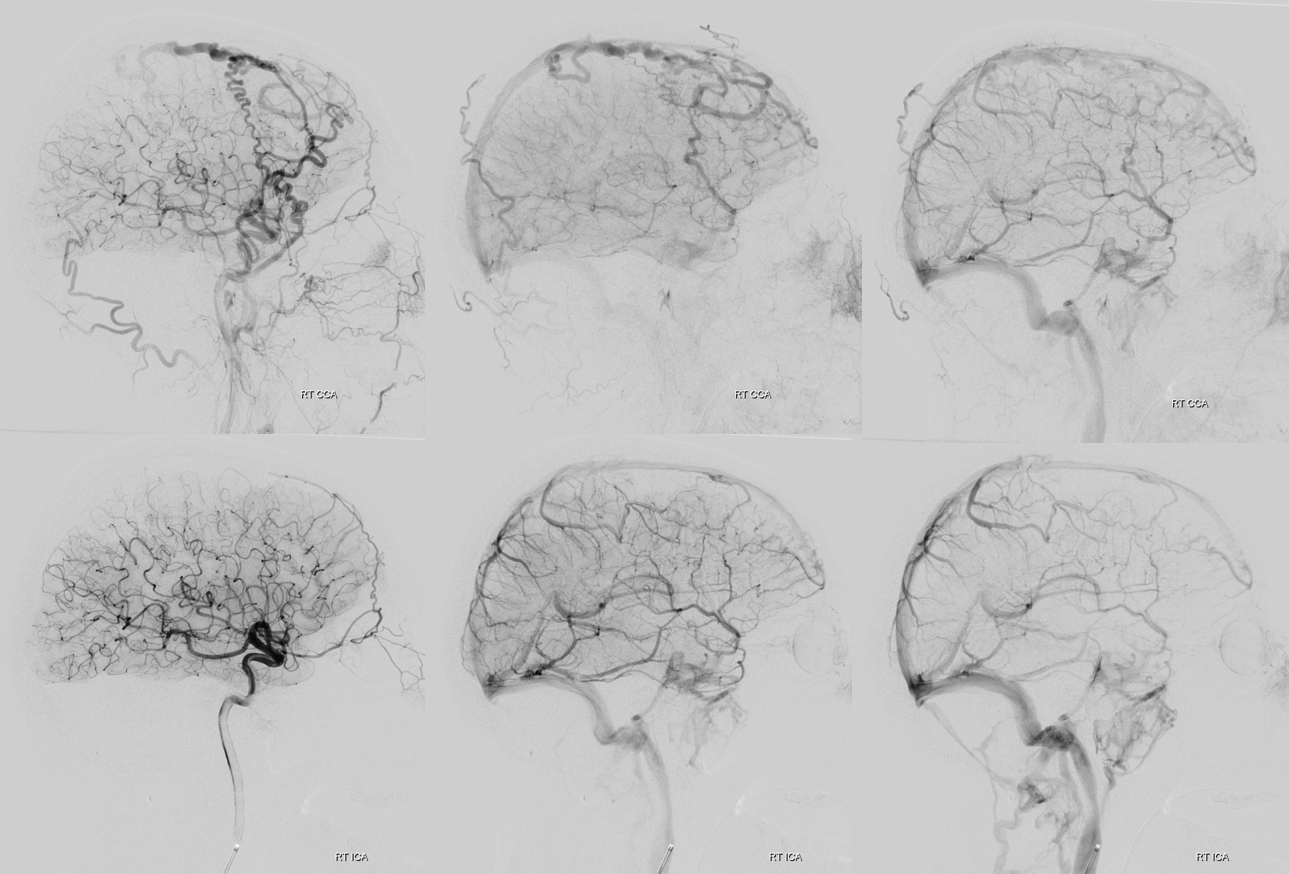

For example. To get venous phase of right ica injection, for Artis Q — choose 5 second DSA DCT — dual volume. FOV = 42 cm. Pure contrast. Inject right ICA at 3 cc/sec for 15 ccs — thus 5 second injection. From END of injection to appearance of veins is 3.5 seconds. Thus delay is 5+3.5= 9 seconds rounding up. Usually around 10 sec delay is about right

MIP Fill

SUB

Volume Rendered rotational of SUB — with added fusion of the ECA

Stereo pair

U can do the same for the other side…

And go from there